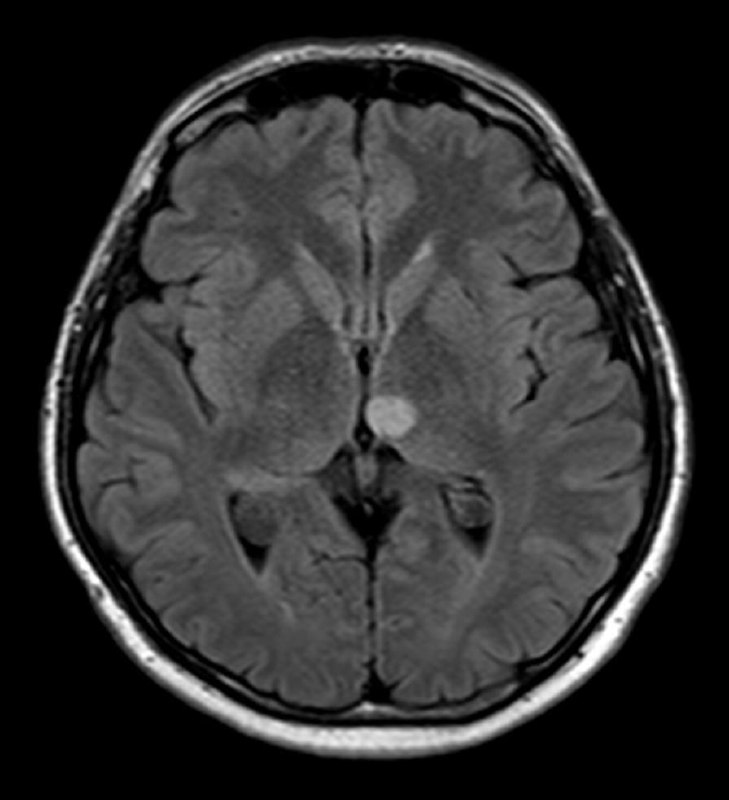

19 сен 2024

Когда рак простаты видно вот так, как здесь - исследование не вызывает отвращения, в отличие от случаев, когда приходится писать PIRADS-3..

Другое дело, что мы ж о пациентах заботимся, а не о себе, любимых, и каждый PIRADS-3 для пациента, все же, лучше, чем легко и непринуждённо обнаруживаемый, как в данном случае, PIRADS-5.

Пожелаем этому мужчине 75 лет успехов в лечении и минимума неприятных ощущений, которыми, неизбежно, такое лечение сопровождается.